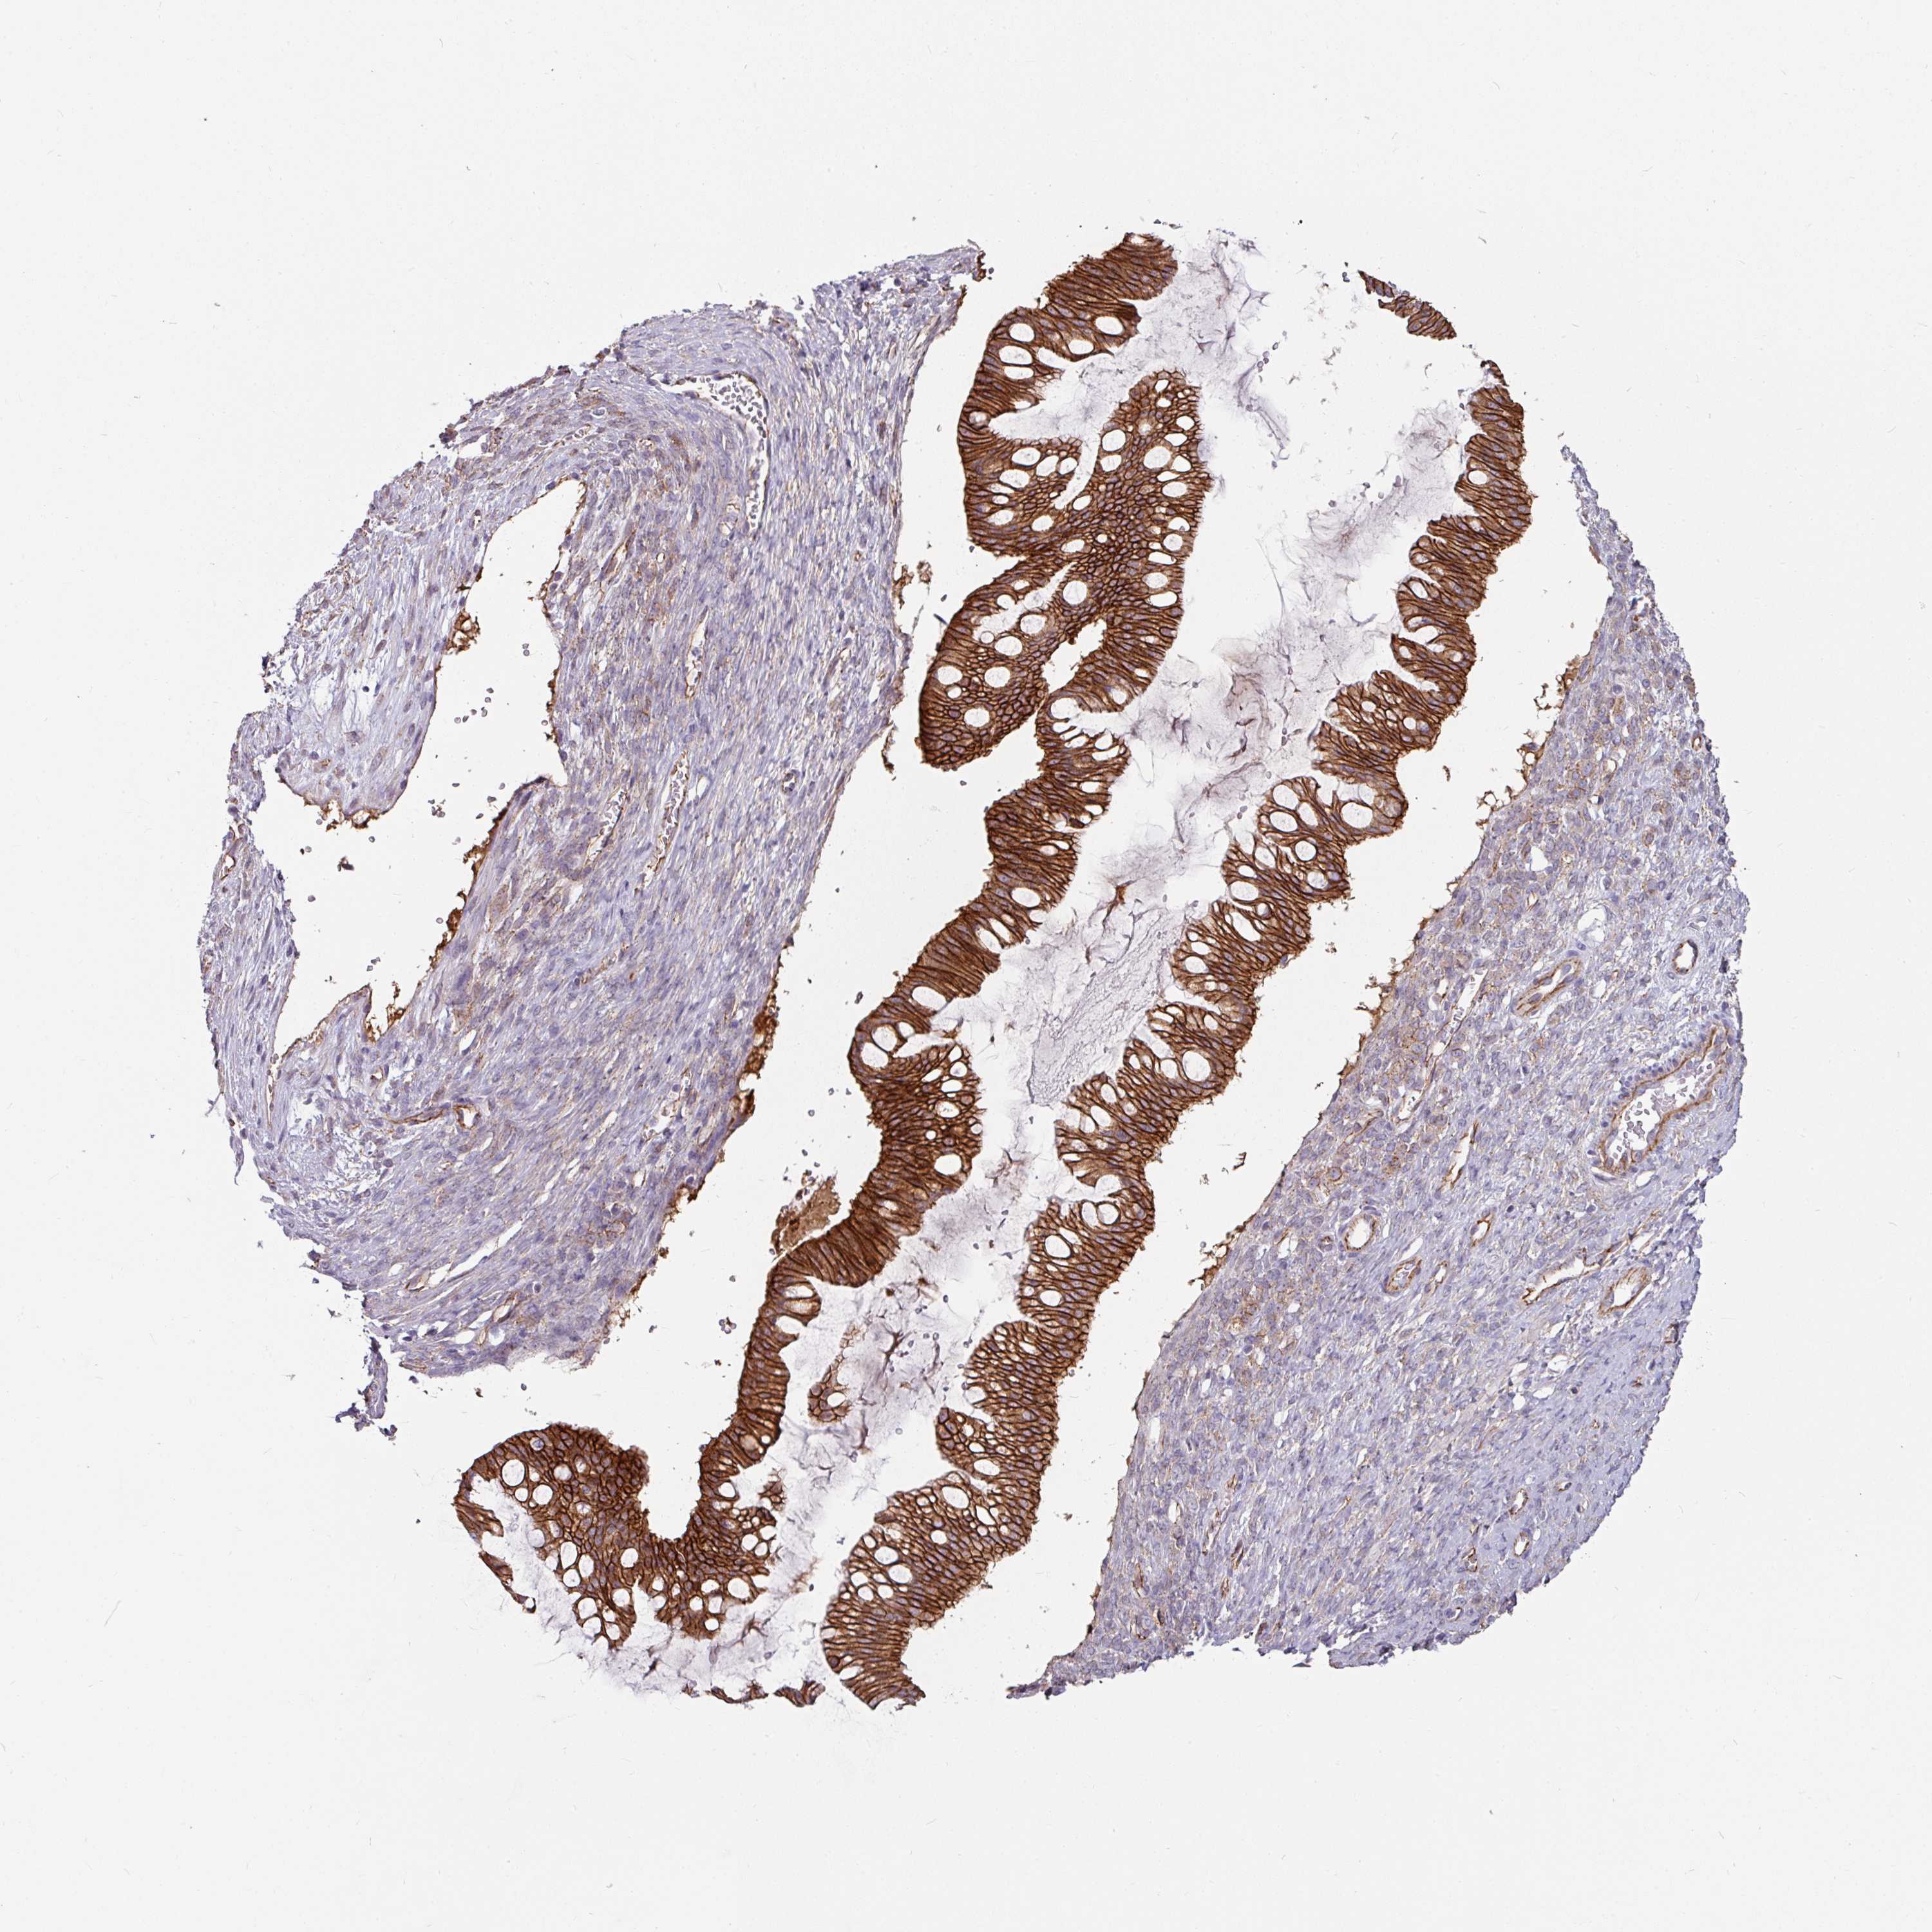

OVARIAN CANCER - Protein expressioni

A mouse-over function shows sample information and annotation data. Click on an image to view it in a full screen mode. Samples can be filtered based on level of antibody staining by selecting one or several of the following categories: high, medium, low and not detected. The assay and annotation is described here.

Note that samples used for immunohistochemistry by the Human Protein Atlas do not correspond to samples in the TCGA dataset.

Antibody stainingi

Antibody staining in the annotated cell types in the current human tissue is reported as not detected, low, medium, or high, based on conventional immunohistochemistry profiling in selected tissues. This score is based on the combination of the staining intensity and fraction of stained cells.

Each image is clickable and will lead to virtual microscopy that enables deeper exploration of all samples and also displays staining intensity scores, fraction scores and subcellular localization as well as patient and tissue information for each sample.

Antibody HPA032047

Antibody CAB002139

Cystadenocarcinoma, serous, NOS

Carcinoma, endometroid

Cystadenocarcinoma, mucinous, NOS

Carcinoma, NOS